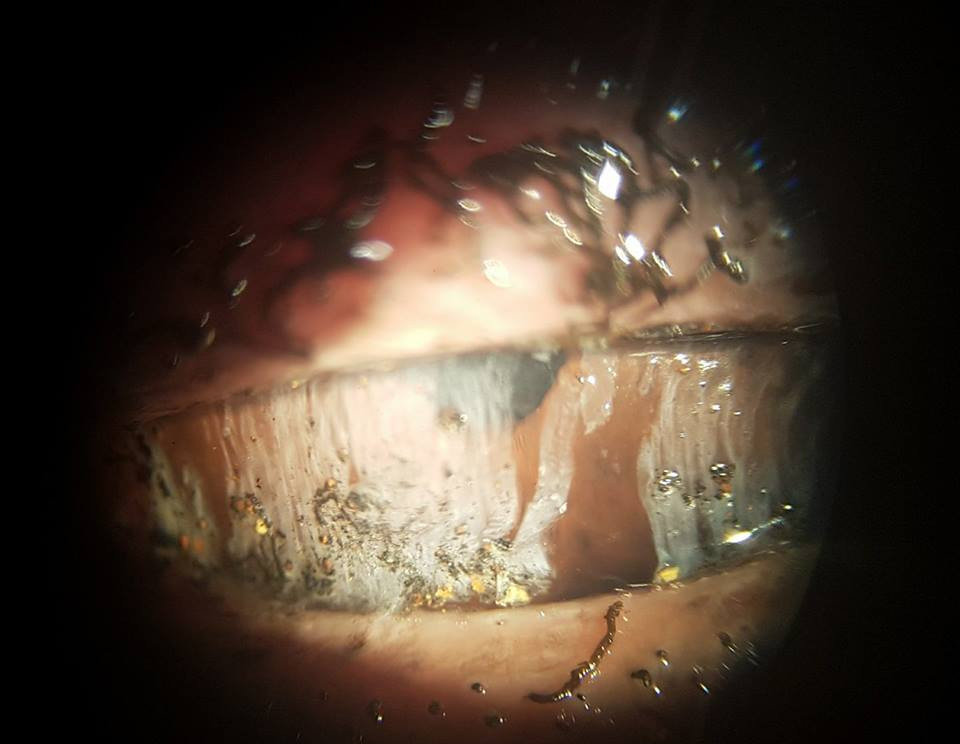

Mắt bị chấn thương, nhãn cầu có nhiều dị vật do pháo nổ.

Theo bác sĩ Trần Ánh Dương (Bệnh viện hữu nghị Việt Nam - Cuba Đồng Hới), các trường hợp chấn thương mắt do pháo nổ nhập viện, có một trường hợp mắt trái bị vỡ nhãn cầu, hai trường hợp hai mắt bỏng kết giác mạc độ 2 và trường hợp còn lại mắt trái bị xuất huyết tiền phòng độ IV.

Tất cả các trường hợp này còn bị dị vật cắm sâu vào kết - giác mạc. Ngoài tổn thương tại mắt, các bệnh nhân còn bị tổn thương phần mềm vùng mặt. Những bệnh nhân này đều sinh sống ở các huyện trên địa bàn tỉnh Quảng Bình.